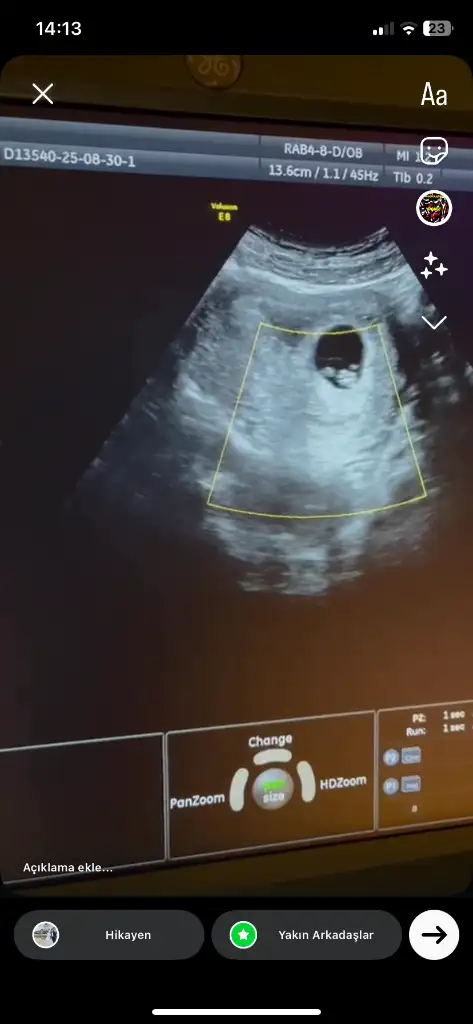

Benimde 13+1 de karından ultrason ile bakıldı tahmin de bulunabilir misiniz 🙏

1000039327.webp